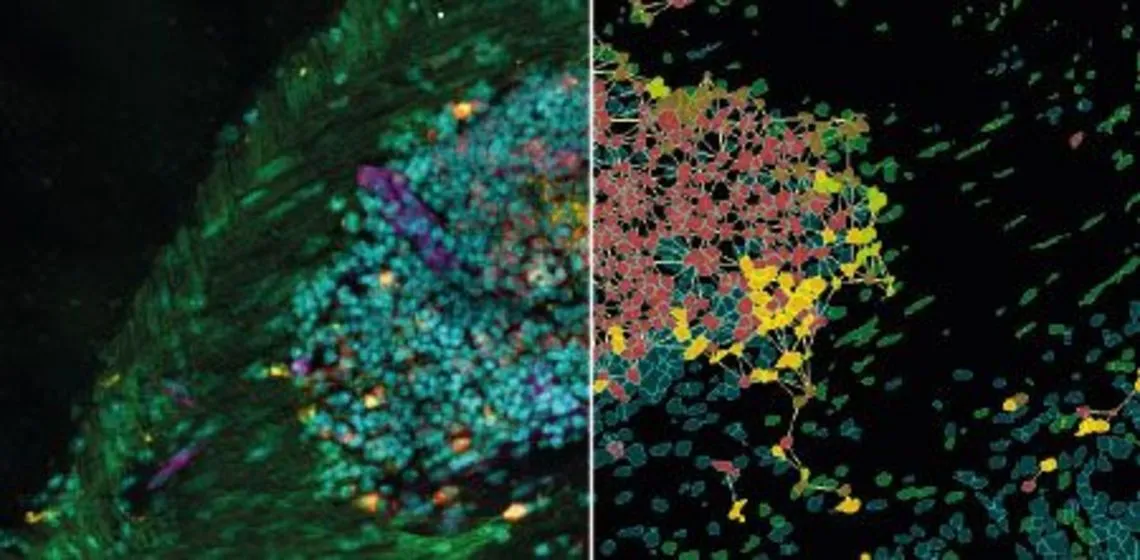

Applications of AI in Cell Segmentation

Accurate cell segmentation is the foundation of tissue cytometry. AI-powered methods, such as deep learning, improve accuracy, reduce errors, and streamline workflows. TissueGnostics integrates AI-based segmentation with phenotyping, spatial analysis, and dot detection.